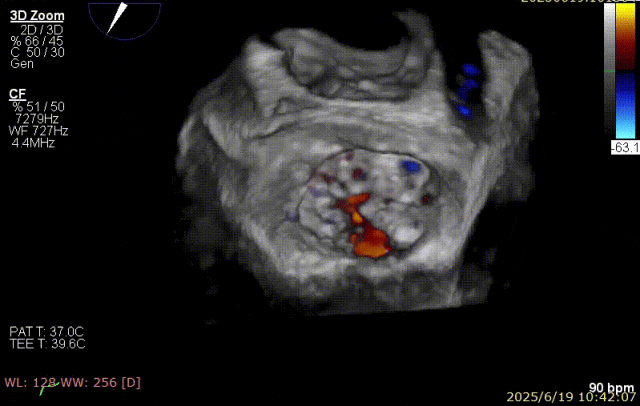

2025 年 6 月 29 日,经过对术前超声和 CT 影像进行深入分析,团队制定了周密手术计划。在麻醉手术中心副护士长刘菊梅的充分术前准备和中国医学科学院阜外医院欧阳文斌教授的指导下,凭借团队的紧密协作和娴熟操作,单纯利用超声影像精确引导,通过导引导管系统经右胸、右房,穿房间隔,建立到达左房通路;经该通路将两枚二尖瓣钳夹成功植入二尖瓣病变部位进行夹持,夹合器位于 3 区及部分 2 区,固定好,运动协调,瓣叶启闭灵活,瓣口轻度反流,二尖瓣平均跨瓣压差 2 mmHg。手术圆满完成。

手术步骤

器械植入后二尖瓣 AP 径约 35 mm,CC 径约 39 mm;夹合器固定好、组织桥稳定,前瓣夹闭后瓣叶长度 25 mm,后瓣夹闭后瓣叶长度 7 mm;二尖瓣开放好,瓣口呈大小双孔,二尖瓣瓣口面积约 2.8 cm²,平均压差 1 mmHg,关闭可,二尖瓣反流明显减轻(从术前反流 4+显著改善至 1+),手术全程无需体外循环支持,无需输血,无需射线全超声引导。患者术后第二日回普通病房,患者恢复良好,术后第五日即出院。